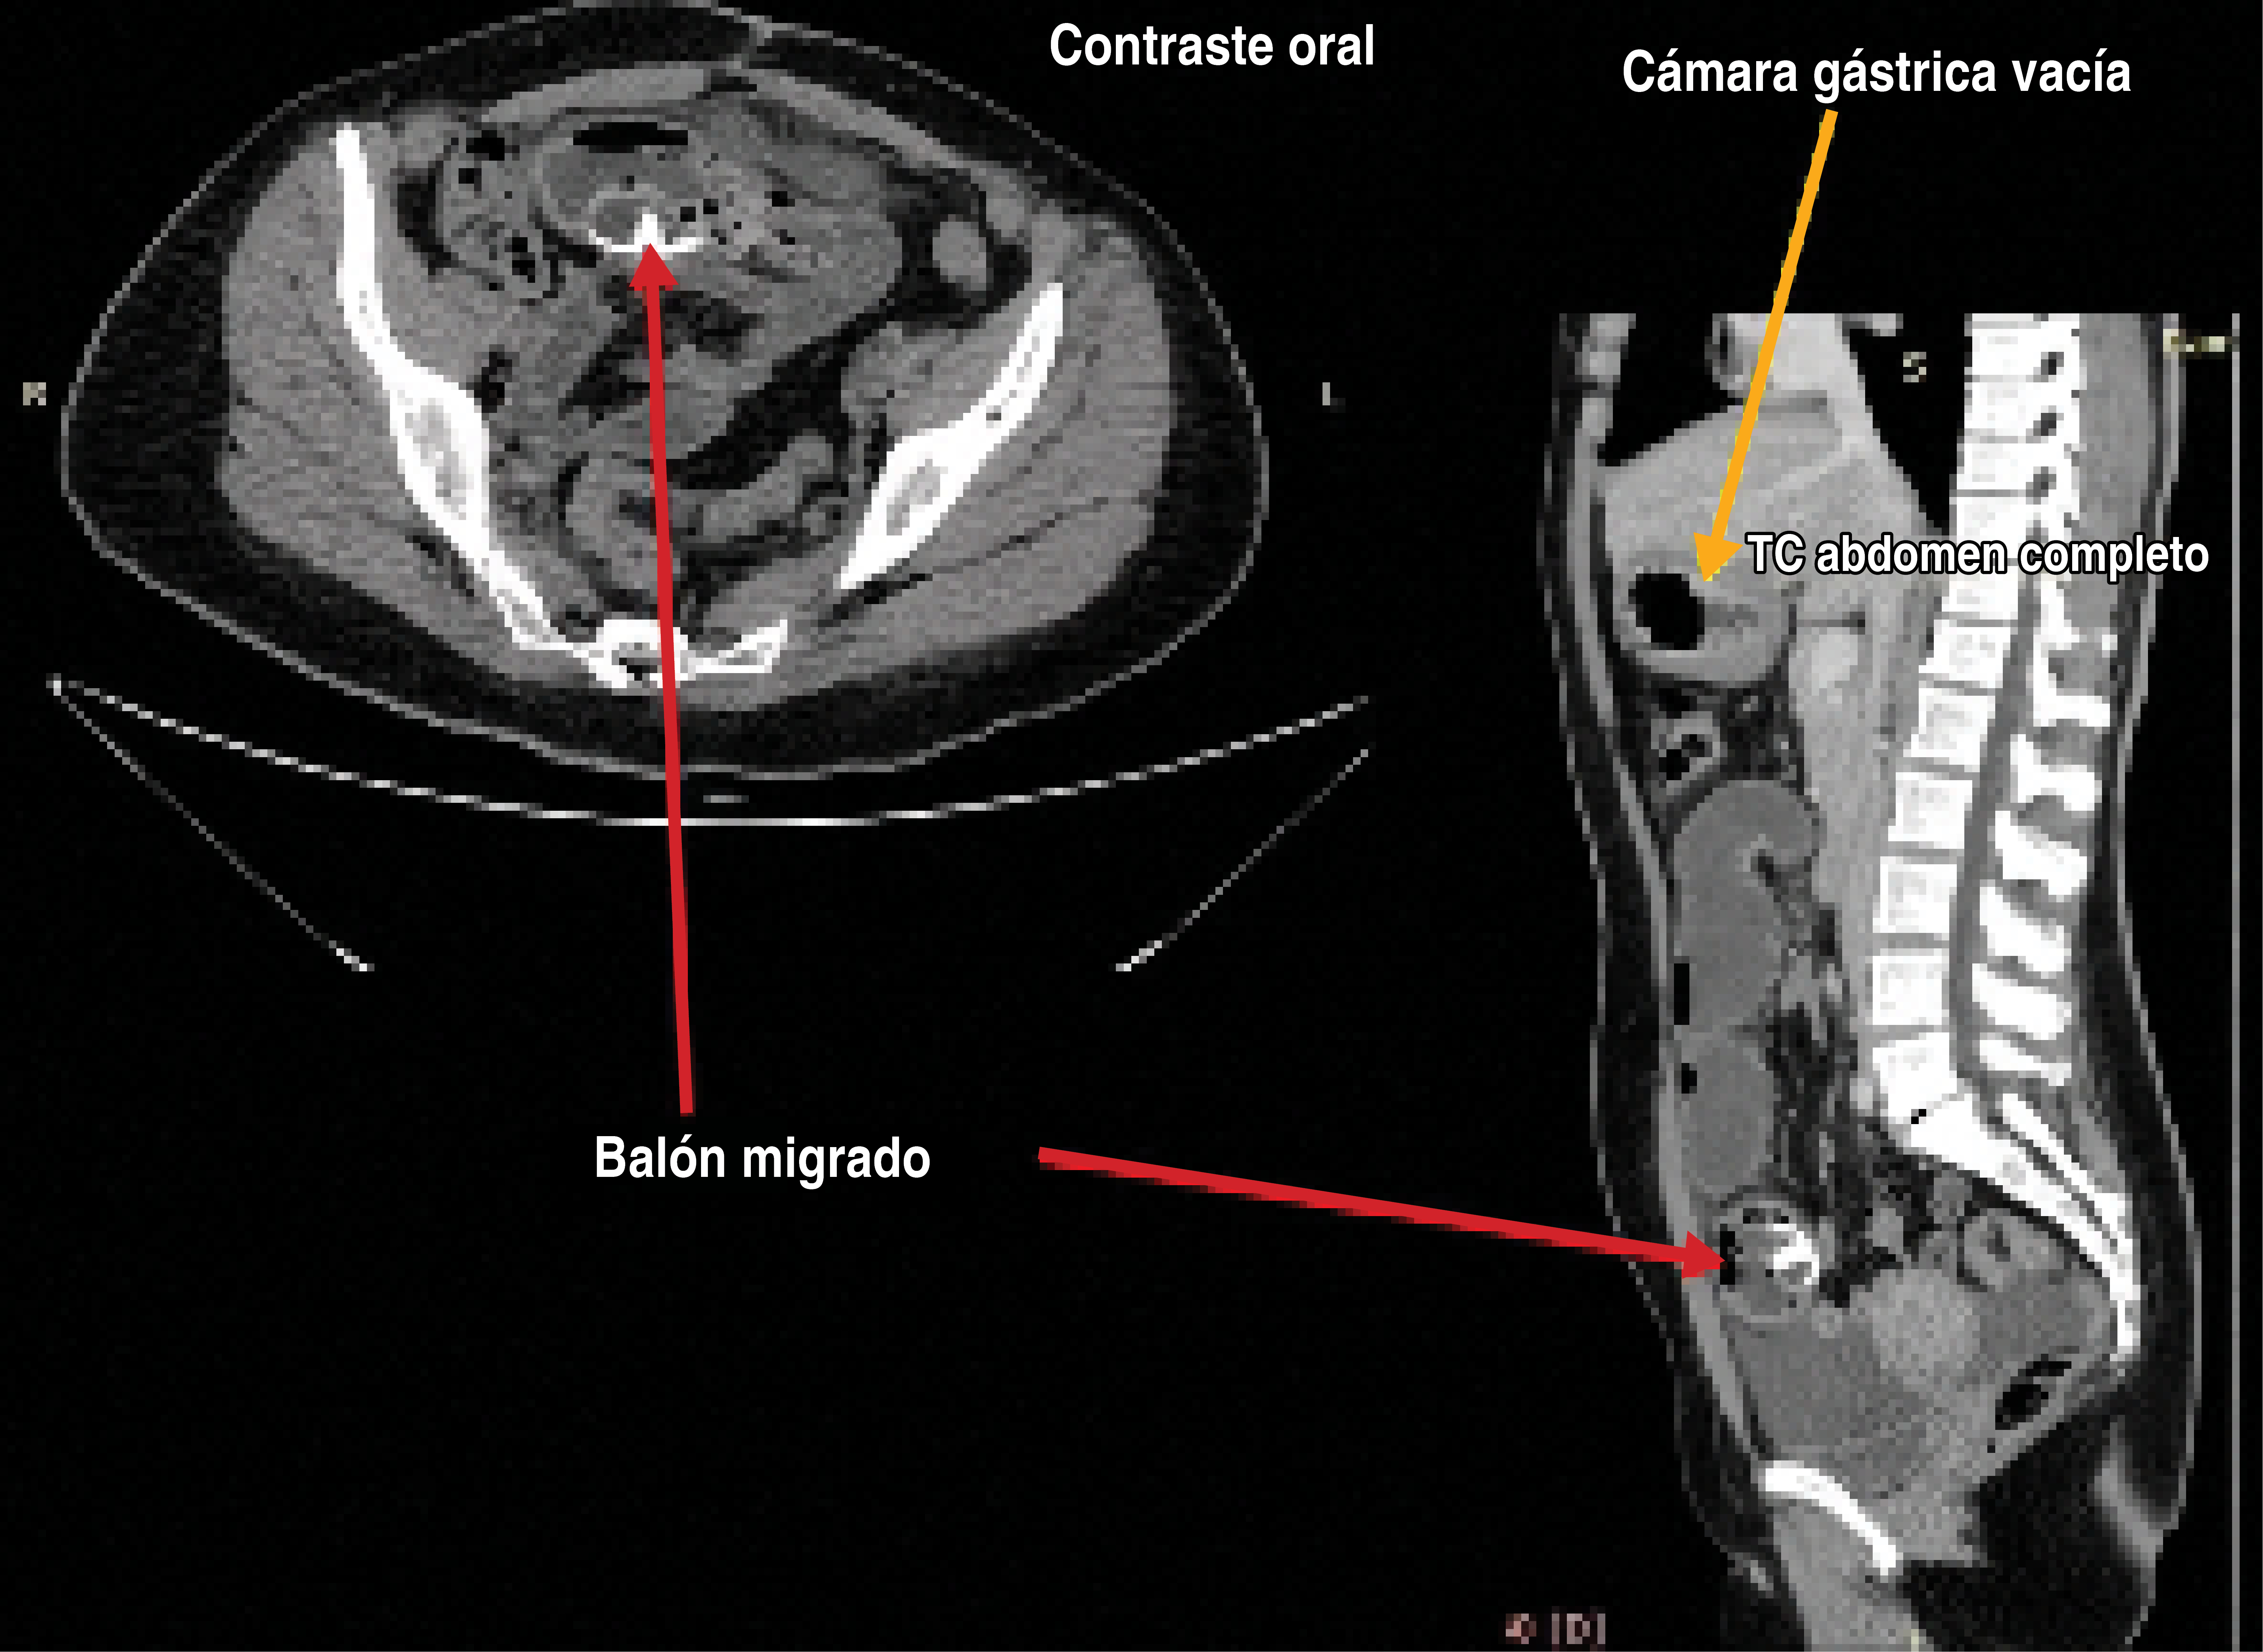

Introduction: the most common cause of intestinal obstruction after Roux-en-Y gastric bypass (RYGB) is internal herniation and can be resolved by laparoscopic approach. The objective of this paper is to present three unusual causes of intestinal obstruction in bariatric patients that can be resolved by a minimally invasive approach. Report of cases: The first case presents a 31-year-old patient with a history of Roux-en-Y gastric bypass 3 years previously who presented with an occlusive syndrome. An intussusception was diagnosed and successfully managed with laparoscopy. The second case is a 37-year-old patient who had a gastric balloon placed 1 year prior to admission, who did not attend withdrawal at 6 months, goes to the hospital with an occlusive picture, diagnosing distal impaction of the balloon, which was successfully extracted laparoscopic route. Last case, a 39-year-old patient with a history of Roux-en-Y gastric bypass 9 years prior to admission with occlusive syndrome. Laparoscopy revealed an 8 cm impacted phytobezoar in the terminal ileum. It was manually removed using a 5 cm disposable retractor through the umbilicus. Results: two cases were successfully resolved laparoscopically and the third was extracted extracorporeally, but with a laparoscopic approach. No patient presented early or late complications. Conclusions: the causes of intestinal obstruction in this series of bariatric cases are unusual and all could be resolved by minimal invasion with no mortality to report.

Figure 1

Figure 2